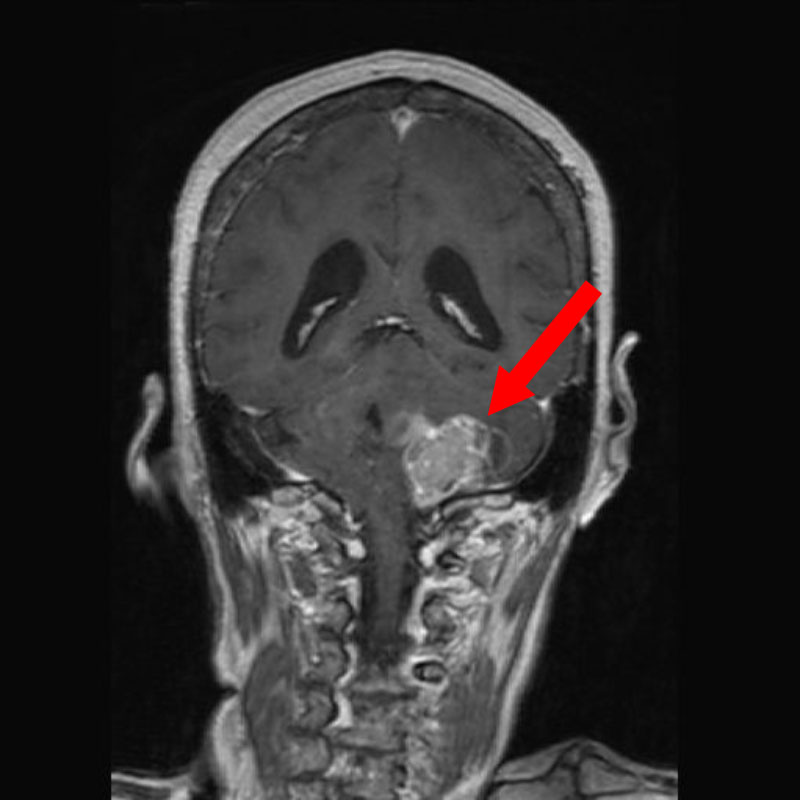

708

'25年12月

60代

左後頭葉腫瘍

頭蓋内腫瘍摘出術

No.’25_110 手術前1

No.’25_110 手術前2

No.’25_110 摘出 前

No.’25_110  摘出 中

No.’25_110 摘出 後